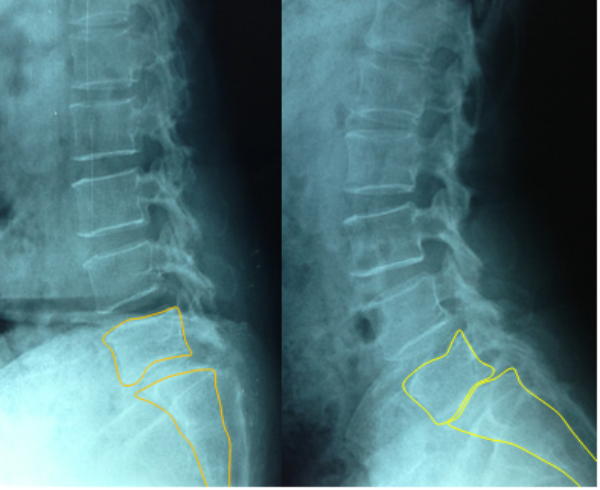

Trượt ở L45 chiếm tỷ lệ cao nhất với 50% (17 BN), có 11 BN (32,3%) trượt ở 2 tầng đốt sống. Phần lớn bệnh nhân trợt độ 1 theo phân loại của Meyerding (31 BN chiếm 91,2%). Nguyên nhân trượt chủ yếu là do thoái hóa 28 BN (82,3%), có 4 BN trượt sau mổ cột sống trong đấy có 2 bệnh nhân sau mổ thoát vị đĩa đệm và 2 bệnh nhân sau mổ cố định cột sống. Có 29 BN (86,3%) có dấu hiệu mất vững cột sống biểu hiện bằng tăng độ động trên xquang vùng cột sống thắt lưng cúi ưỡn.

Trên xquang: Trượt ở L45 chiếm tỷ lệ cao nhất với 50% (17bn), có 11bn (32,3%) trượt ở 2 tầng đốt sống tương tự với các nghiên cứu khác trượt ở vị trí L45 gặp nhiều nhất, tuy nhiên tỷ lệ trượt 2 tầng trong nghiên cứu của chúng tôi gặp nhiều hơn như Nguyên Vũ chỉ có 7,8% bệnh nhân trượt 2 tầng [4]. Nguyên nhân trượt chủ yếu là do thoái hóa 28 BN (82,3%), có 4 BN trượt sau mổ cột sống trong đấy có 2 BN sau mổ thoát vị đĩa đệm và 2 BN sau mổ cố định cột sống, tỷ lệ này khác so với các nghiên cứu của Nguyên Vũ và Võ Văn Thanh đều thấy tỷ lệ gặp nguyên nhân hở eo là nhiều hơn [4], [5]. Phần lớn bệnh nhân trượt độ 1 theo phân loại của Meyerding (31 BN chiếm 91,2%), tỷ lệ này cao hơn so với Nguyễn Vũ (trượt độ 1 chiếm 72,3%) [4]. Có 29 BN (86,3%) có dấu hiệu mất vững cột sống biểu hiện bằng tăng độ động trên xquang vùng cột sống thắt lưng cúi ưỡn.